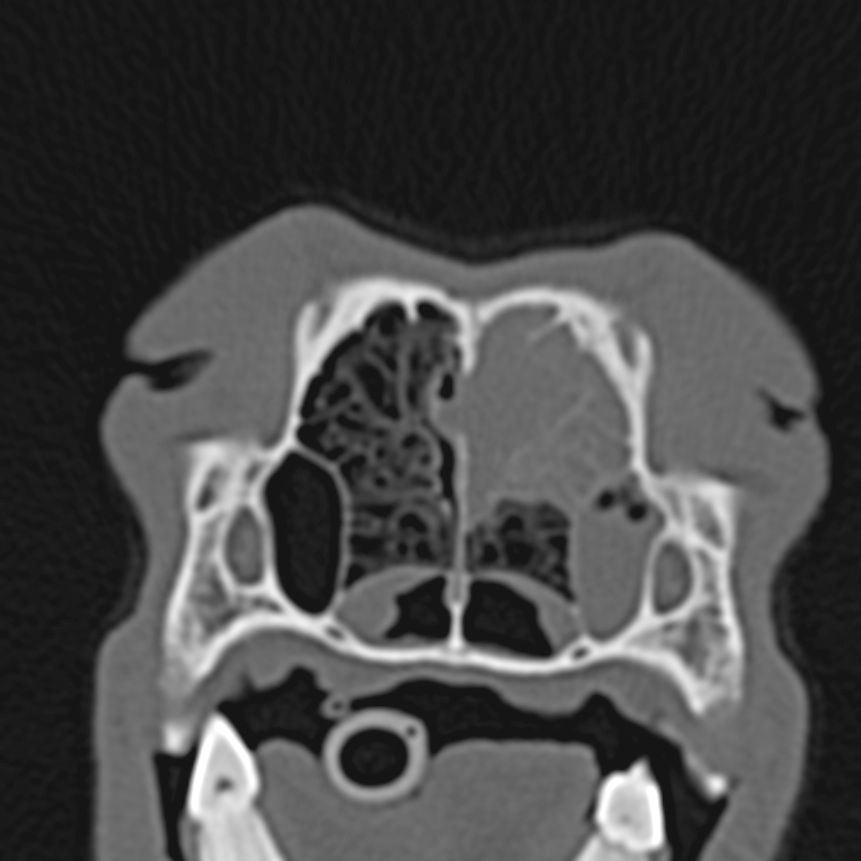

Das ist kein Röntgen,.sondern ein CT Bild. Man sieht das Innere der Nase eines Hundes. Dieses arme Tier hat die Hälfte seiner Nase voll mit Tumormassen, Die Nasenscheidenwand ist nun auch schon kaputt. Wenn wir solche Aufnahmen wirklich mal brauchen ist es auch kein Problem mal einen Fall an eine ausgestattete Kollegin im Umkreis zu überweisen und zusammen zu urteilen.